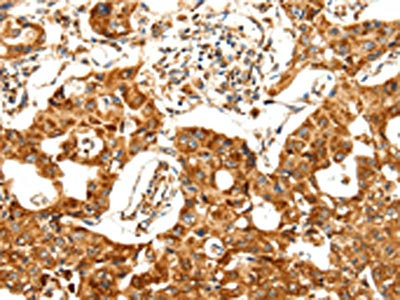

The image on the left is immunohistochemistry of paraffin-embedded Human liver cancer tissue using CSB-PA549792(DOPEY1 Antibody) at dilution 1/25, on the right is treated with synthetic peptide. (Original magnification: ×200)

The image on the left is immunohistochemistry of paraffin-embedded Human lung cancer tissue using CSB-PA549792(DOPEY1 Antibody) at dilution 1/25, on the right is treated with synthetic peptide. (Original magnification: ×200)